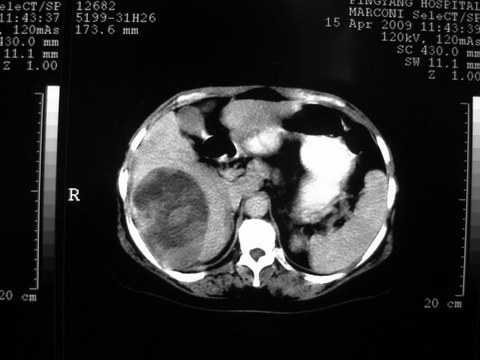

患者 女 51岁 两天前感觉上腹疼,无明显诱因,b超示肝右叶囊实性占位,边缘清楚,其内回声不均匀,ct增强如图,大家看看是什么 ,病人一年前及两月前b超检查只是提示胆囊炎

外院术后,证实肝癌合并出血

本例有2个特点:1,病灶发展迅速,(2月前正常)

2,囊实性,且并边界清晰光滑,呈右后叶赘生性。

可以排除源发肝脏恶性肿瘤和良性肿瘤。

只有转移,出血或炎症可以发展迅速!

特点:1,病灶发展迅速,(2月前正常)[br] 2,囊实性,且并边界清晰光滑,呈右后叶赘生性。囊性区无强化,实性部分较多轻度强化,边界欠清。考虑囊腺癌或囊腺瘤。

出病理 中分化肝细胞癌合并出血